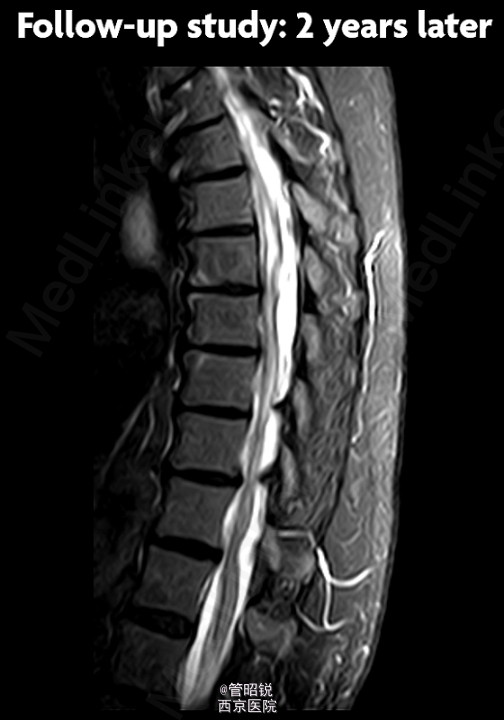

患者,男,71岁,急性头痛和腰痛。 慢性脊髓囊性蛛网膜炎是蛛网膜下腔出血的罕见并发症。此并发症被认为是由于溶血导致的蛛网 膜炎性反应,导致其纤维化和脊膜的继发性增厚,包括硬脑膜。纤维可形成囊腔包裹脑脊液,从而压迫脊髓,引起脊髓病和脊髓空洞积水征。一般保守治疗或者手术 CT显示轻微的脑室内出血,另外,在部分脑裂出可见模糊的高密度影,提示蛛网膜下腔出血。DSA双侧大脑前动脉狭窄。T1WI显示胸腰段脊髓腔内出血,定位在蛛网膜下。随访2年后,显示蛛网膜下的腔隙在脊髓表面形成扇贝样改变。随访3年腔隙仍然存在,以致脊髓表面继发性畸形。(来源于AJNR)